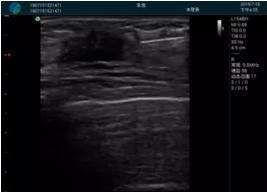

M20查看:囊內(nèi)回聲均勻,邊界清晰,囊壁光滑

M20引導抽吸術(shù)后囊腫消失,原區(qū)域空腔形成,脂肪層與腺體層架構(gòu)發(fā)生改變